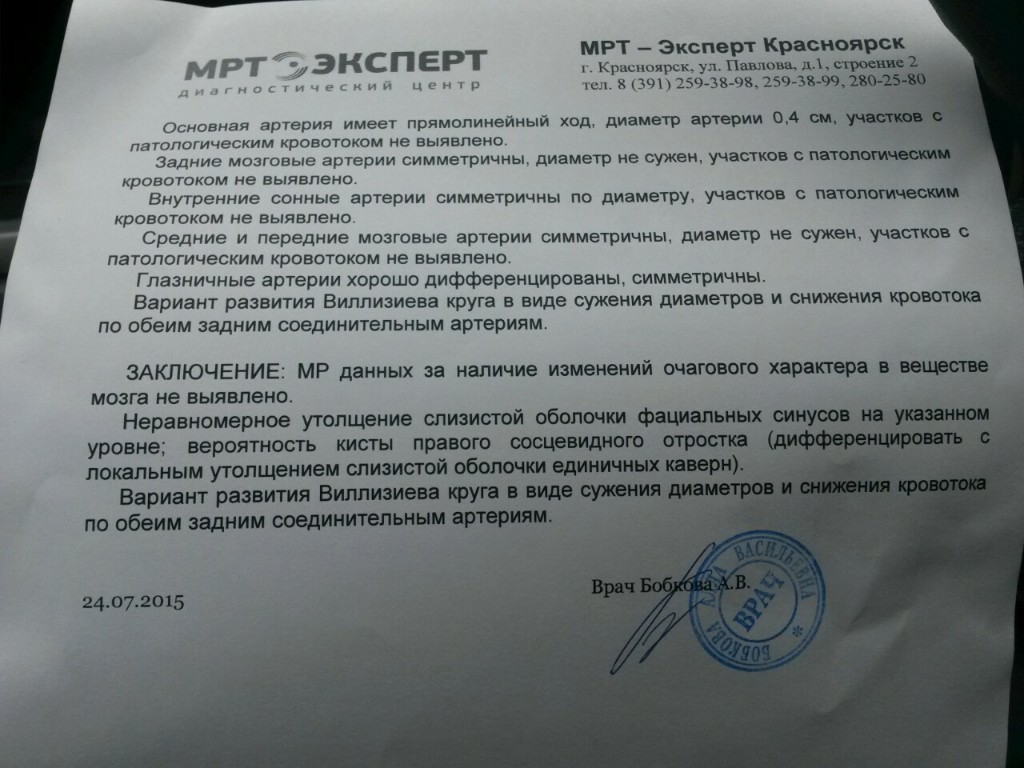

МРТ головного мозга: Расшифровка снимков и Интерпретация

Раздел: Визуальные уроки